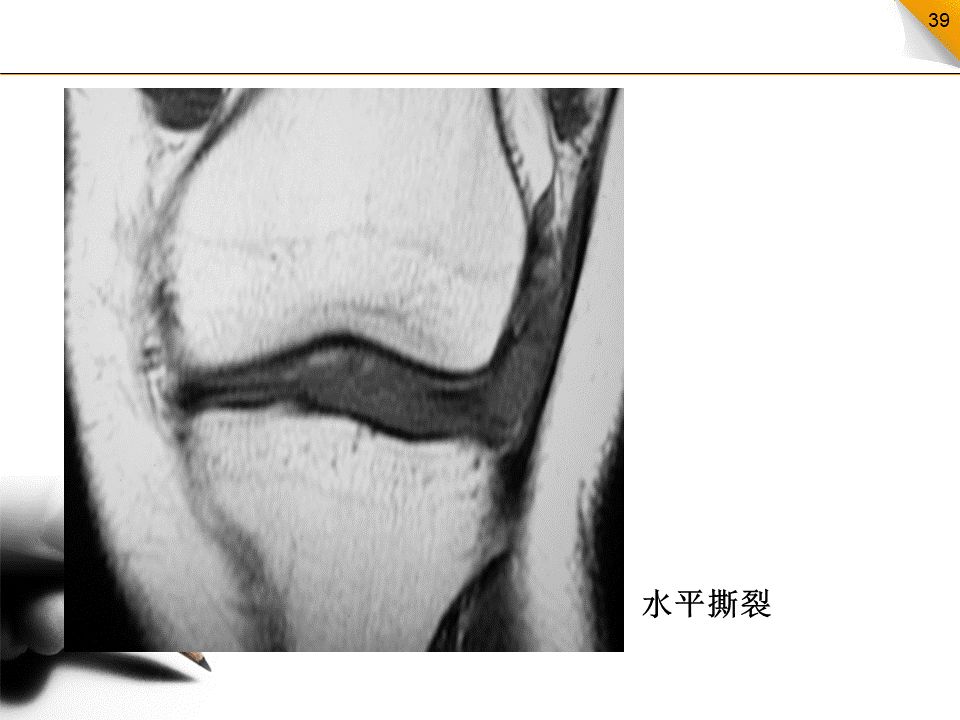

半月板撕裂的分类

水平撕裂:比较少见,高信号的方向与胫骨平台平行,内缘达半月板的游离缘垂直撕裂:其高信号的方向与胫骨平台垂直斜行撕裂:最常见类型,高信号的方向与胫骨平台成一定的角度纵行撕裂:高信号的方向与半月板的长轴方向平行放射状撕裂:高信号的方向与半月板的长轴方向垂直,好发于外侧半月板的内1/3部

• 水平撕裂容易在半月板的囊缘形成半月板囊肿